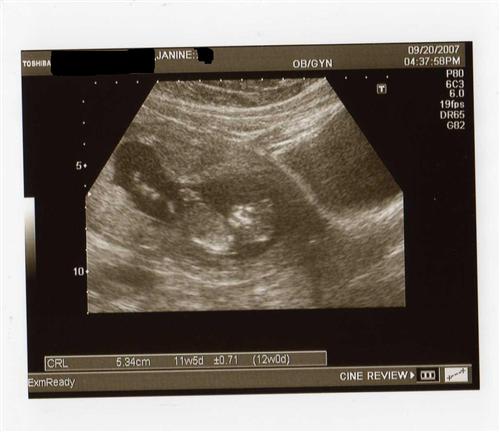

Had 12 week sono last night w/pics

The baby was sleeping, I had to cough to wake it up. You can see how it was sleeping...with it's hands behind his/her head-I guess it's comfy in there! Oh, and I think our child looks like an alien...

Does anyone know what the other black circle to the right is? We didn't think to ask. If it was another baby, it would be full, so I don't think it is that.